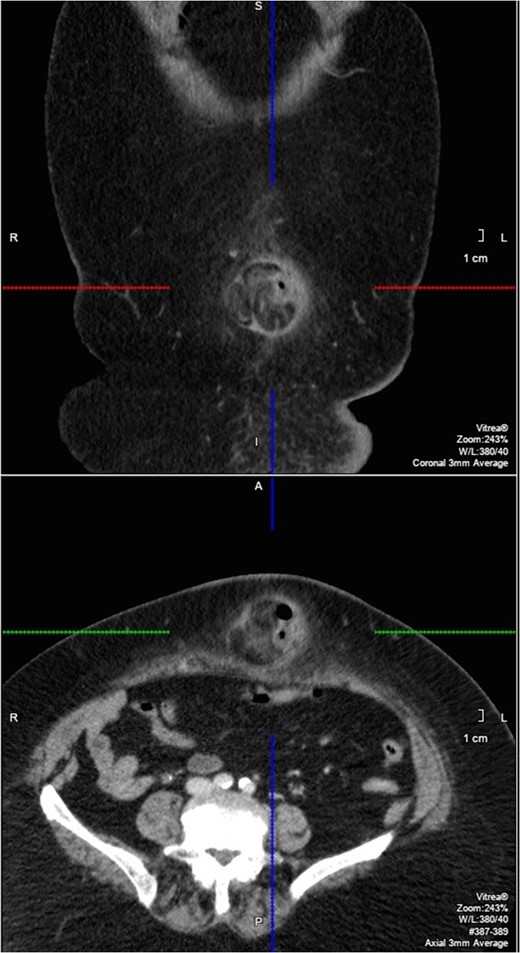

Coronal and axial slice of the CT showing the paraumbilical hernia (within marked areas).